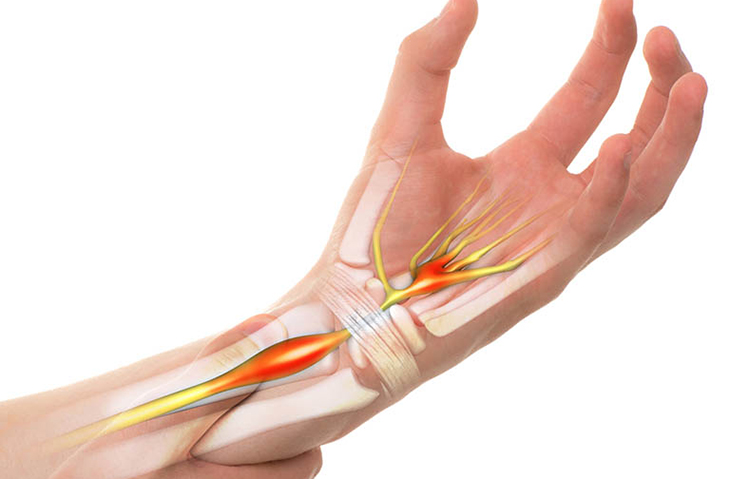

b. Hội chứng ống cổ tay

Điều trị:

- Nẹp cổ tay: Đeo nẹp cổ tay vào ban đêm để giảm áp lực lên dây thần kinh.

- Thuốc chống viêm: Dùng thuốc giảm đau kháng viêm không steroid (NSAID).

- Phẫu thuật: Nếu các phương pháp khác không hiệu quả, phẫu thuật giải phóng ống cổ tay có thể được thực hiện.

Tê bì chân tay do hội chứng ống cổ tay